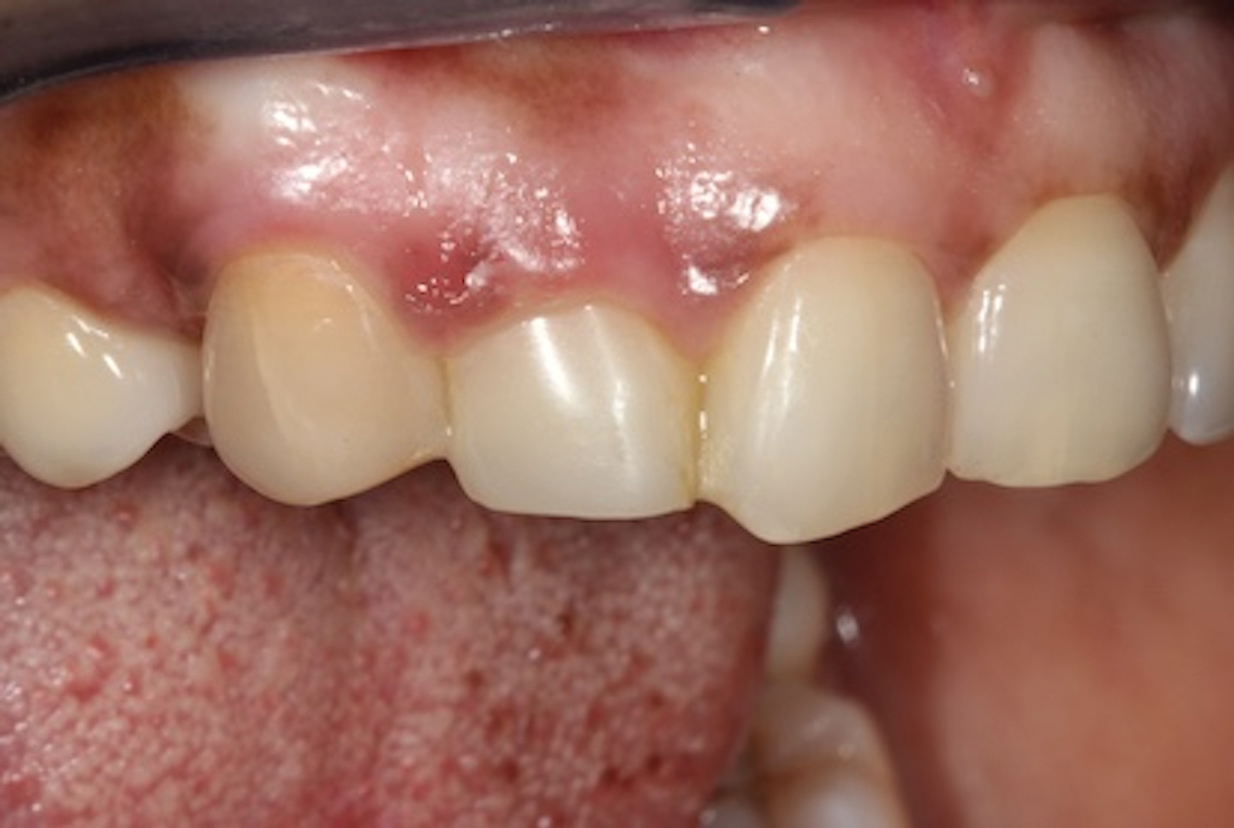

(14.) Three-month posttreatment close-up right lateral view of the final bridge. Note how the soft tissue at the site demonstrates adequate growth over the resin pontic, which will later translate into excellent esthetics for the implant-supported crown.

Figure 14